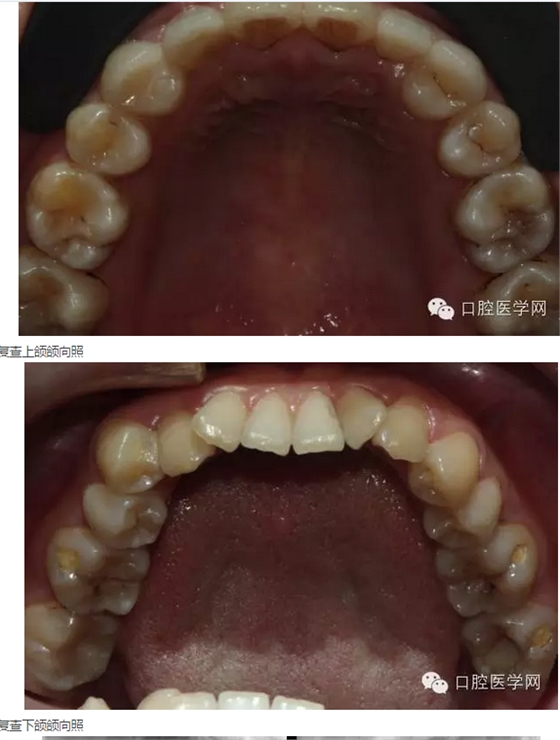

2015年5月3日:戴牙。(見(jiàn)圖24-30)(拍照時(shí)22、24排齦線尚未取出)

來(lái)源于口腔醫(yī)學(xué)網(wǎng)